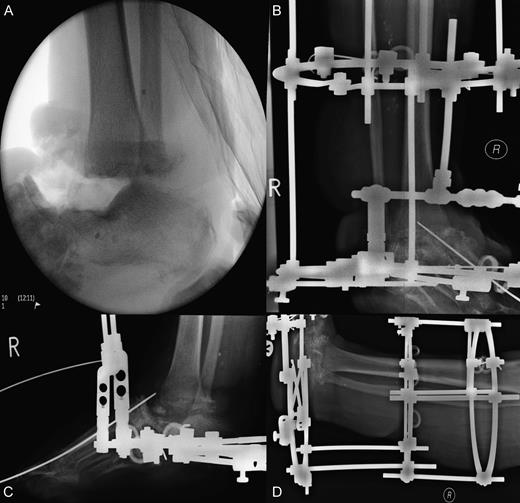

A 55-year-old woman presented with an open 3C Gustilo–Anderson fracture. Her medical history included rheumatoid arthritis, osteoarthritis, ischaemic heart disease, diabetes mellitus and asthma. Soft tissues were closed using a free flap from the left thigh and a flap from the right lower limb. Bony injury was treated with open reduction internal fixation with screw fixation of the first and third metatarsals into the talus with restoration of the medial and middle columns achieved using cannulated screws. Additional stability was achieved by plate fixation of the medial and lateral columns (Fig. 1). The treatment was deemed successful, and the patient was discharged.

Open 3C Gustilo–Anderson injury. (A and B) Theatre images of open 3C Gustilo–Anderson fracture. (C and D) Radiographs illustrating open reduction internal fixation (ORIF) (screw fixation of the first and third metatarsals into the talus). The ORIF using cannulated screws allowed restoration of the medial and middle columns of the foot. Plate fixation of the medial and lateral column was conducted to achieve additional stability.